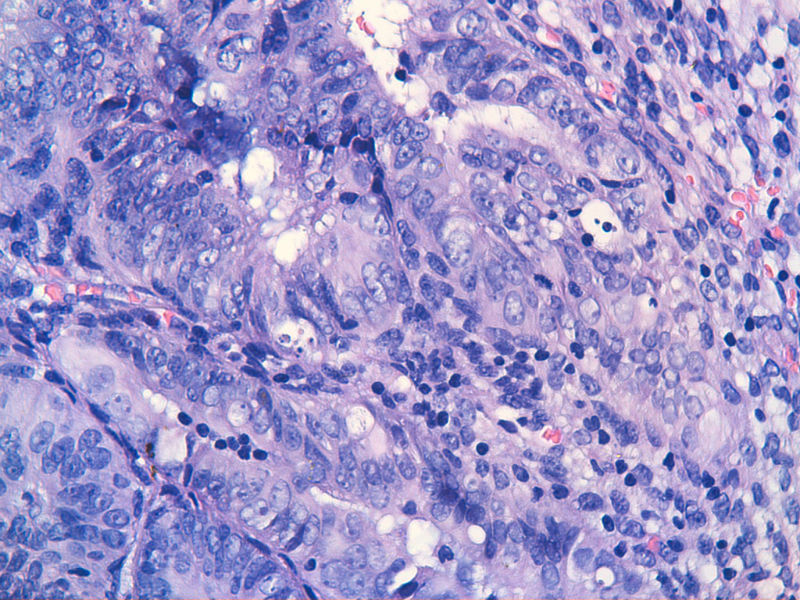

图13是做为正常对照的,图7、8、9、12显示的核大小不一,空泡状,形状不规则。女,48岁,宫血半年